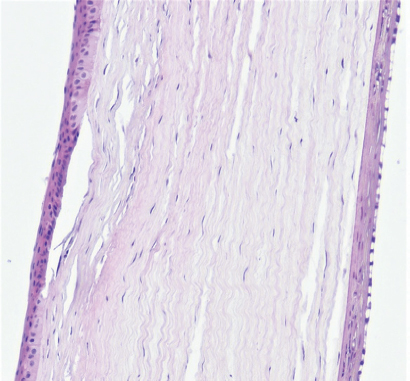

Режим 6. При данной мощности в месте воздействия роговица имеет нехарактерный вид. Эпителий полностью покрывает место вмешательства, однако базальные клетки эпителия кубические, сам эпителий истончён, неплотно прикреплён к строме. Строма в области повреждения практически на 1/4–1/3 толщины образована неплотно лежащими коллагеновыми волокнами с большим числом фиброцитов и единичными лимфоцитами. Десцеметова мембрана и энодотелий без изменений (рис. 4).

Рис. 4. Фрагмент роговицы через 3 мес. после воздействия в подгруппе 1а. Фульгурация, режим 6. Окраска гематоксилином и эозином. Увеличение ×40

Fig. 4. Fragment of the cornea 3 months after exposure in subgroup 1a. Fulguration, mode 6. Stained with hematoxylin and eosin. Magnification ×40